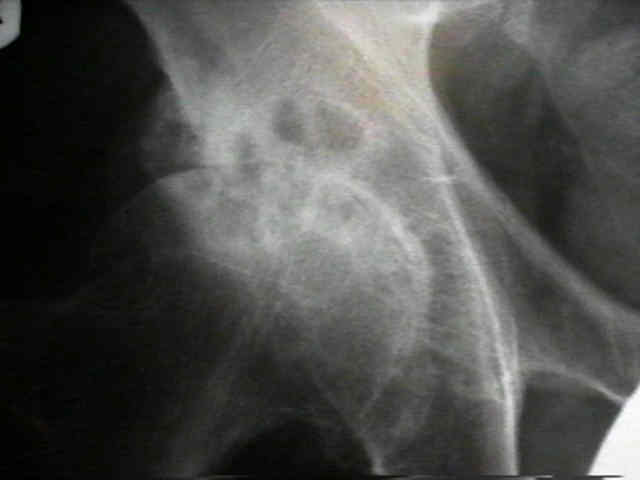

Hip Osteoarthritis

clinical features

Hip Osteoarthritis 2

• pain on wt-bearing felt in the groin, buttock, or medial thigh;

• trendelenburg gait will decrease mechanical stress on joint and thereby lessen pain (see forces acting on hip joint);

• pain during sleep results from loss of protective function of muscular splinting;

• in some cases, a patient w/ OA of the hip will experience acute hip pain which often correlates w/rupture of subcondral cyst into the joint;